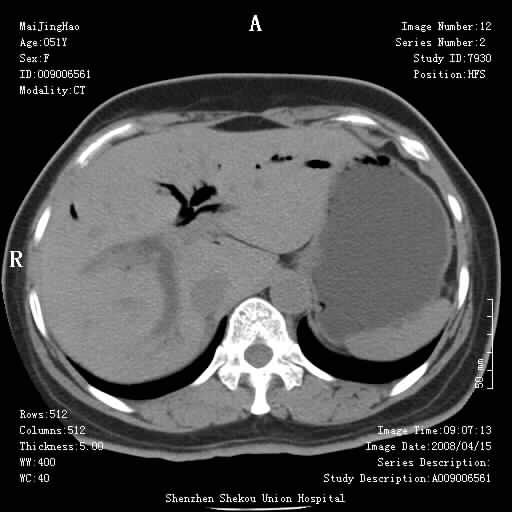

以下是引用余辉在2008-4-26 8:55:00的发言:[br]患者有结石史,此次腹痛4小时,胆总管全程扩张,应有胆总管末端梗阻,此次仍考虑胆结石症,积气不外两种原因,一种是结石下移时肠道内气体逸入,其次为产气菌感染。(倒数第三幅图像于扩张之胆总管末端似可见稍高密度影,考虑为结石影)

以下是引用yangyudong333在2008-4-26 6:17:00的发言:[br]1胆系感染,可能为金葡菌感染,2考虑有化脓性胆管炎致胆总管扩张,3胰头部增大,建议做增强

以下是引用听蝉观竹在2008-4-26 11:41:00的发言:[br]胆道手术分两种情况:[br]1、如果仅仅做胆囊切除手术,肝内胆管不会积气,只会出现胆总管代偿扩张,因为奥迪氏括约肌依然功能正常胆道与外界并不相通;[br][br]2、胆囊切除+胆总管空肠吻合手术(即roux-y式),则肝内胆管会出现积气,只是因为胆管与小肠相通,气体来源于小肠。这是临床十分常见的手术。[br][br]这个病例应该是胆囊切除+胆总管空肠吻合手术,是正常手术后表现,并不是胆道感染的表现。

以下是引用宇宙ct在2008-4-26 10:43:00的发言:[br][br] 胆囊切除术后胆管常因代偿而出现扩张,肝内胆管也经常会出现积气征象;胰头强化后再诊断。 [br] [br]

以下是引用听蝉观竹在2008-4-27 10:10:00的发言:[br]关于胰头大小问题有几种测量方法和正常值:[br][br]1、直量法:横径<4cm;[br]2、胰头横径与相邻层面椎体横径的比值为二分之一,超过椎体横径就提示胰头增大;[br]3、正常组成年人肠系膜上动、静脉水平夹角正常值范围为4.9°~34.7°大于35°提示胰头增大。[br][br]上述方法只是一种具体的判断,是“量”的评估,更重要的是“质”的评估:一是观察边缘是否光滑,有无局部隆起,有无分叶;二是观察密度(增强,尤其在动脉期和门脉期)是否均匀。[br][br]所以对于胰头是否有异常不仅仅是是目测可以解决问题的,不要轻易就说“胰头增大”。还有一个问题就是测量胰头应该在增强ct上进行,这样可以避免将血管测量进去。[br][br]为什么啰嗦讲怎么多,因为我们实际工作中同样存在影像科医生和临床医生动不动就说胰头增大,说是胰头癌。大家看看是不是这种情况?[br][br] 我个人观点-----本病例的胰头不增大。[br][br][本贴已被 听蝉观竹 于 2008-4-27 10:12:41 修改过]